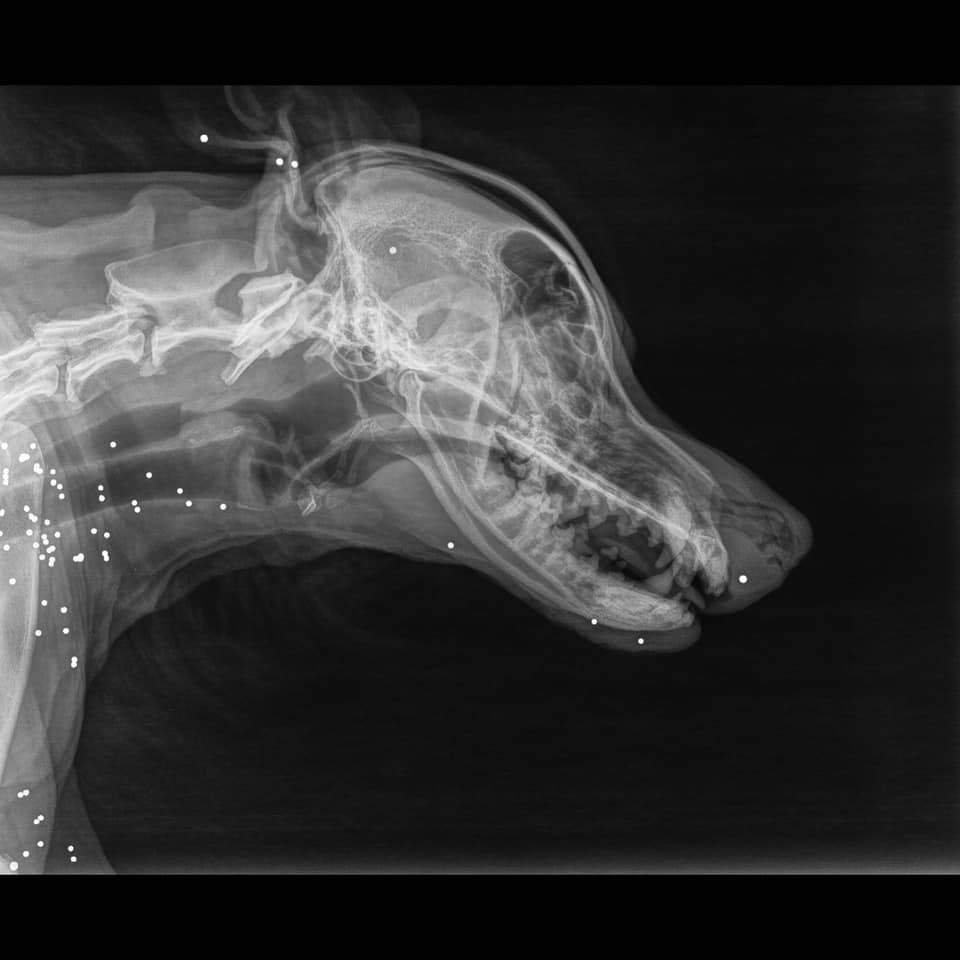

Την επομένη ο Σταλόνε δείχνει σημάδια ζωής. Μεγάλος σε ηλικία, γεμάτος κατάγματα ΚΑΙ αμέτρητα σκάγια. Δυο τα πιθανά σενάρια. Είτε κάποιος τον πυροβόλησε και βγήκε στο δρόμο σαστισμένος και το πάτησε ΚΑΙ αμάξι είτε τον είχαν πυροβολήσει πιο παλιά και τον πάτησε και αμάξι εκείνη τη μέρα. Πιθανότερο το πρώτο σενάριο. Επίσης διαγνώστικε ΚΑΙ Ερλίχια ΚΑΙ Καλαζάρ ΚΑΙ Διροφυλαρίωση!

Τις ώρες που το ζωάκι ήταν υπό αναισθησία για τις ακτινογραφίες, εμφανίστηκε στο κτηνιατρείο ο άνθρωπος που το χτύπησε με το αμάξι. Αναφέρει ότι κάλεσε την τροχαία για να καταγράψει το περιστατικό και ήθελε μεν να δει το ζωάκι αλλά και να κάνει μήνυση στο δήμο για να του φτιάξουν τη ζημιά 500 ευρώ που είπε ότι έγινε στο αυτοκίνητό του από το χτύπημα.